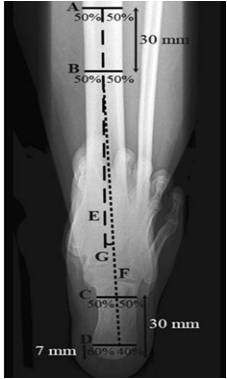

后足长轴位

1.         确定胫骨长轴E

2.         确定跟骨长轴F

距跟骨最低处7mm处做水平线C,分为3:2

距跟骨最低处30mm处做水平线D:分为1:1